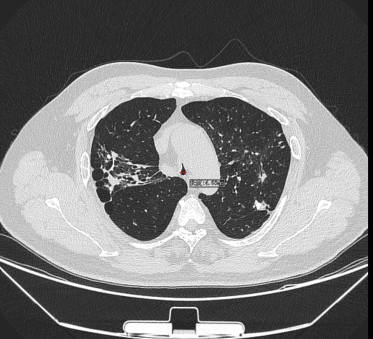

日前,患者趙先生(化名)因進(jìn)行性呼吸困難來到河南省胸科醫(yī)院尋求治療,經(jīng)檢查確診為支氣管結(jié)核導(dǎo)致氣管中下段重度瘢痕性狹窄,最窄處直徑僅約3mm,且局部軟骨環(huán)破壞、塌陷,這意味著支撐氣道的結(jié)構(gòu)遭到損毀,通氣功能嚴(yán)重受損,且因狹窄部位靠近隆突,治療操作風(fēng)險(xiǎn)極高,稍有不慎就可能導(dǎo)致大出血、氣道完全閉塞等致命并發(fā)癥。

在硬質(zhì)支氣管鏡引導(dǎo)下,手術(shù)團(tuán)隊(duì)首先對(duì)狹窄部位進(jìn)行球囊擴(kuò)張。隨后,將術(shù)前根據(jù)患者三維CT數(shù)據(jù)定制的Y型硅酮支架精準(zhǔn)覆蓋于氣管狹窄段。該支架確保與患者自身的氣道解剖結(jié)構(gòu)完美貼合,實(shí)現(xiàn)最佳支撐效果,并最大限度減少粘膜刺激增生等特點(diǎn)。支架展開后穩(wěn)定支撐于隆突及雙側(cè)主支氣管,氣道狹窄立即得到解除。